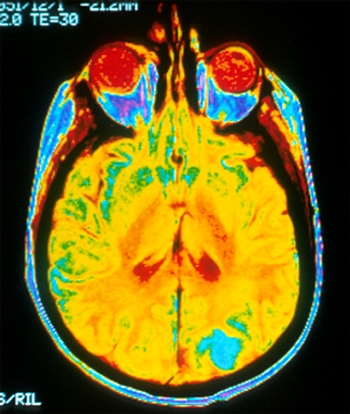

Images: Horner syndrome, neurofibroma, sciatica, ulnar neuropathy, intradural extramedullary schwannoma (neurinoma), moyamoya syndrome and stroke.